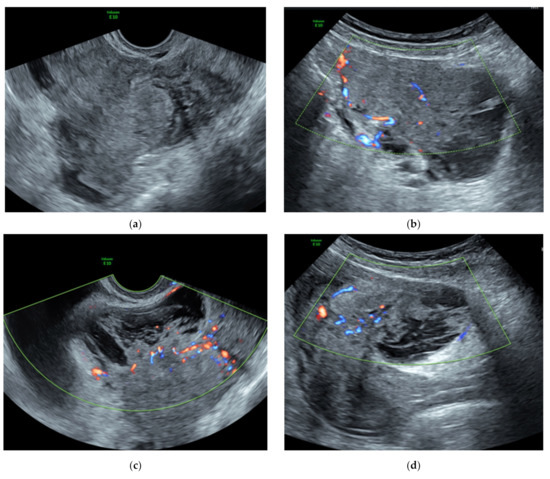

3.1. Preoperative Assessment

| Pelvic Ultrasound | Magnetic Resonance Imaging | During Surgery |

|